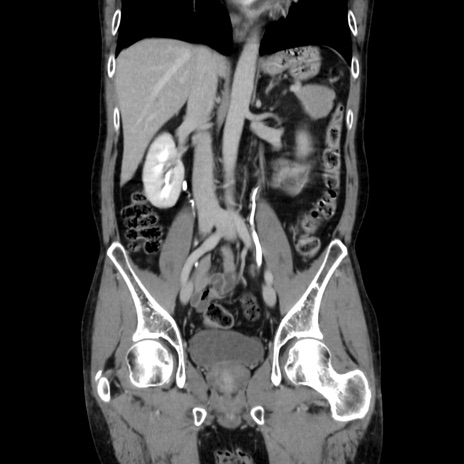

症例37(冠状断像)

【症例】40歳代 男性

【主訴】腹痛

【現病歴】4時間ほど前に電車に乗車中に臍部上より腹痛出現。徐々に増悪し起立困難となり、救急外来受診。生ものは数日食べていない。今朝お雑煮を食べた。

【身体所見】BT 36.8℃、BP 117/84mmHg、HR 91/min、SpO2 97%、苦悶様、腹部:臍上部広範囲圧痛あり、反跳痛±

【データ】WBC 8100、CRP 0.03